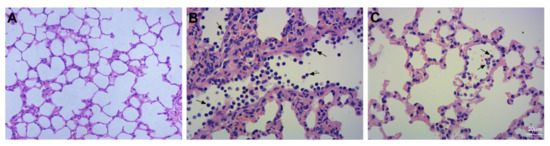

Background: Mesenchymal stem cell (MSC) intervention has been associated with lung protection. We attempted to determine whether mouse gingival-derived mesenchymal stem cells (GMSCs) could protect against bleomycin-induced pulmonary fibrosis. Methods: Mice were divided into three groups: control (Con), bleomycin (Bl), and bleomycin + MSCs (Bl + MSCs). Mice were treated with 5 mg/kg bleomycin via transtracheal instillation to induce pulmonary fibrosis. We assessed the following parameters: histopathological severity of injury in the lung, liver, kidney, and aortic tissues; the degree of pulmonary fibrosis; pulmonary inflammation; pulmonary oedema; profibrotic factor levels in bronchoalveolar lavage fluid (BALF) and lung tissue; oxidative stress-related indicators and apoptotic index in lung tissue; and gene expression levels of IL-1β, IL-8, TNF-α, lysophosphatidic acid (LPA), lysophosphatidic acid receptor 1 (LPA1), TGF-β, matrix metalloproteinase 9 (MMP-9), neutrophil elastase (NE), MPO, and IL-10 in lung tissue. Results: GMSC intervention attenuated bleomycin-induced pulmonary fibrosis, pulmonary inflammation, pulmonary oedema, and apoptosis. Bleomycin instillation notably increased expression levels of the IL-1β, IL-8, TNF-α, LPA, LPA1, TGF-β, MMP-9, NE, and MPO genes and attenuated expression levels of the IL-10 gene in lung tissue, and these effects were reversed by GMSC intervention. Bleomycin instillation notably upregulated MDA and MPO levels and downregulated GSH and SOD levels in lung tissue, and these effects were reversed by GMSC intervention. GMSC intervention prevented upregulation of neutrophil content in the lung, liver, and kidney tissues and the apoptotic index in lung tissue. Conclusions: GMSC intervention exhibits anti-inflammatory and antioxidant capacities. Deleterious accumulation of neutrophils, which is reduced by GMSC intervention, is a key component of bleomycin-induced pulmonary fibrosis. GMSC intervention impairs bleomycin-induced NE, MMP-9, LPA, APL1, and TGF-β release. Full article

Figure 1